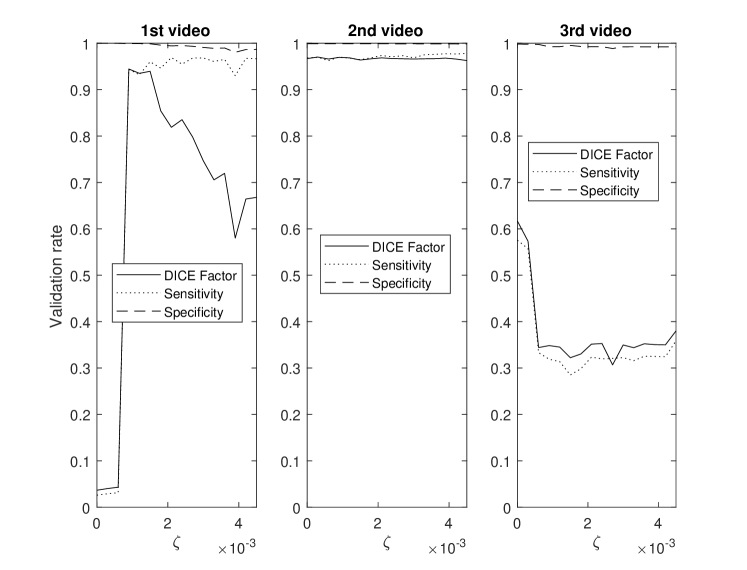

This section demonstrates the robustness of the algorithm for each parameter along with the relative importance of each parameter on the overall performance. This enables the identification and potential removal of weak features from the energy function in order to improve computational efficiency. For this study, the average DICE factor, sensitivity, and specificity of three different clips versus the initial parameters , , , , and are shown in Figs. 5-10. In the all of these figures, one can easily see that the specificity is always very close to one indicating a relatively small rate of .

The three test videos suggest setting to one supports optimal segmentation as shown in Fig. 5. Large values of result in excessive contour shrinking while small values reduce contour smoothness.

The parameter demonstrates optimal performance near zero as per Fig. 6. This strongly suggests that the continuity energy term is a weak feature and hence, can be removed from the energy function.

In Fig. 7, all three videos provide their best performance at a between 0.04 and 0.08, hence, is set at 0.06. In two of the three test videos, the edge energy does not significantly improve the segmentation performance as the curves appear flat around likely resulting from indistinct edges and consequently, providing limited information to improve segmentation results.

Fig. 8 highlights that different videos demonstrate considerable variance in sensitivities versus . Sensitivity was relatively stable for ranging between 0.4 and 0.9, hence was set to 0.8.

For the parameter , the best performance was established between 125 - 175 as shown in Fig. 9. Hence, equal to 150 seems to be an appropriate selection.

Finally Fig. 10 shows that the best performance is obtained when is between 0.0009 and 0.0015 resulting in as an appropriate selection.